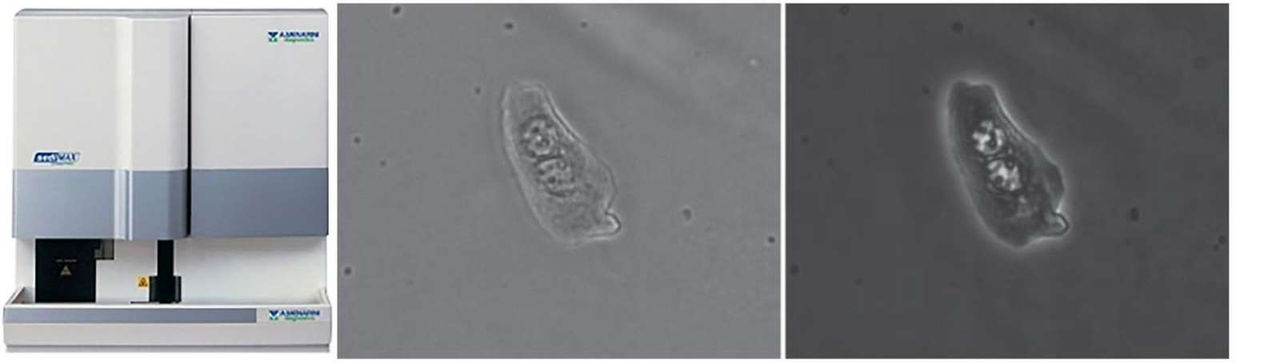

sediMAX conTRUST PRO is the new urine sediment analyzer of the sediMAX series by A.Menarini Diagnostics offering a fully automated approach for the preparation and evaluation of urine samples. sediMAX conTRUST PRO combines bright field and phase contrast microscopy to capture high quality images in one optical system, leading to accurate results. The built-in digital camera takes and saves both BF and PC images with a dual focusing technique. Fifteen different images are acquired for each sample using both methods and evaluated by a neural network.

Improved recognition and accuracy. Compared to brightfield microscopy, phase contrast technology provides improved detection of particles and their morphological details, with increased recognition rates.

Dual view. A new feature to analyze BF and PC images side-by-side simultaneously by means of high power field-like dynamic images, convenient for the analysis of the morphological details of the particles.